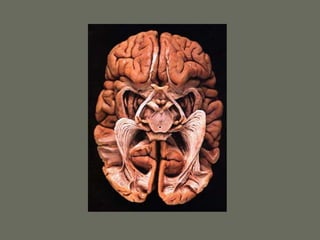

Arteries of the brain

• Anterior circulation – internal

carotid artery, from common

carotid in the neck. Bifurcates to

MCA and ACA

• Posterior circulation – vertebral

arteries that join to form the basilar

artery that will then bifurcate to 2

PCA

Circle of Willis

• Communication between 2 sides –

anterior communicating (a-com)

• Communication between anterior

and posterior circulation – posterior

communicating (p-com)

• Many anomalies may exist